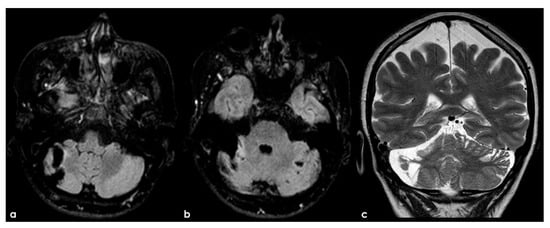

Figure 5.

An example of multifocal cerebellar ischemic lesions in a patient with APS (double positivity). Brain MRI (axial FLAIR in (a,b), coronal T2W sequence in (c) shows the poromalacic evolution of multiple ischemic lesions involving both cerebellar hemispheres (right ≥ left). No causes other than APS were identified in this patients.